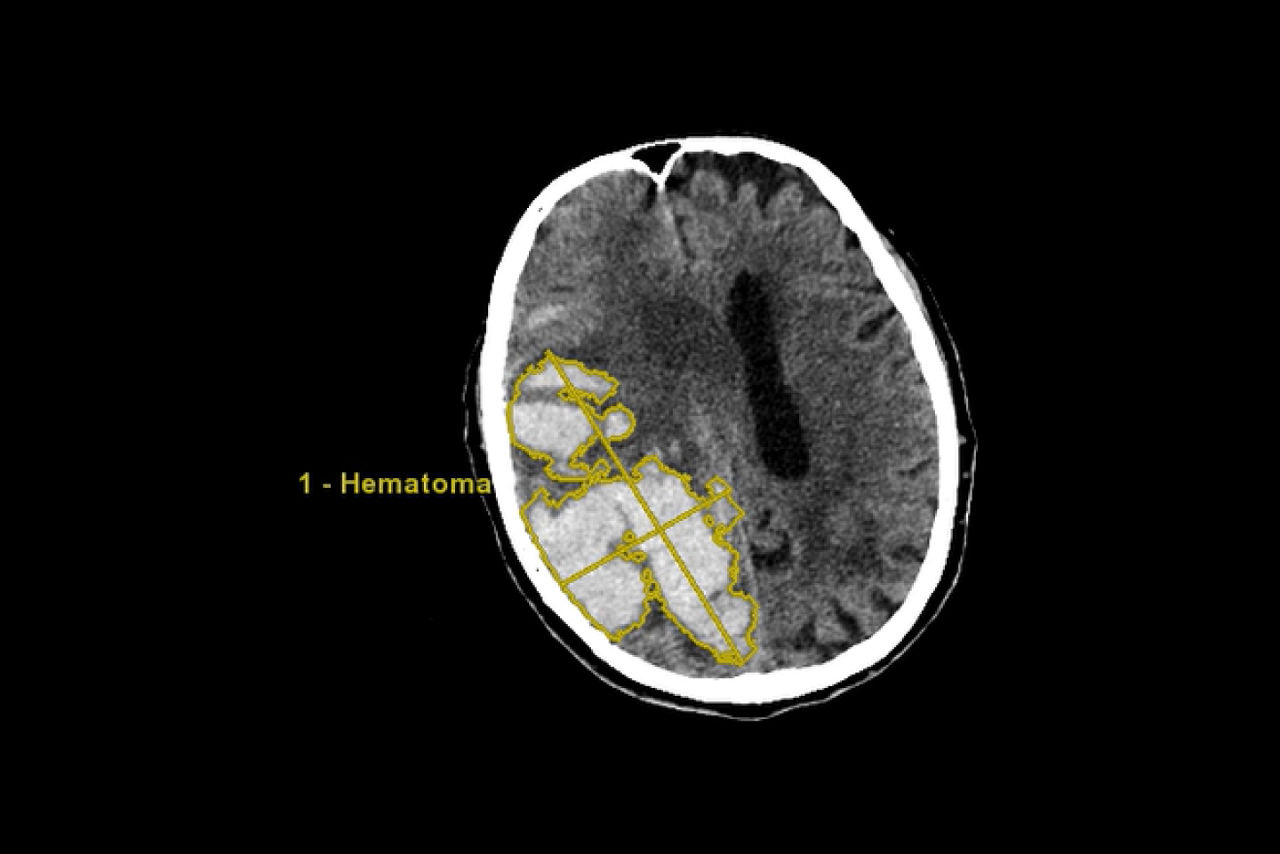

Hematoma

Semi-automated segmentation and sizing of hematoma.

• Semi-automated segmentation and sizing of hematoma

• SmartMesh—an interactive volumetric editing tool

• Track hematoma changes both visually and quantitatively with longitudinal exam workflow